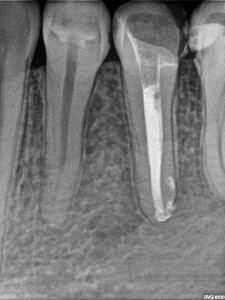

Kanał wypełniono za pomocą Obtury i Systemu B ciekłą gutaperką z użyciem sealera AH+.

Po 10 miesiącach na zdjęciu kontrolnym widać wyraźnie całkowite odbudowanie struktury kostnej okalającej korzeń zęba – drugiego przedtrzonowca w żuchwie po lewej stronie.